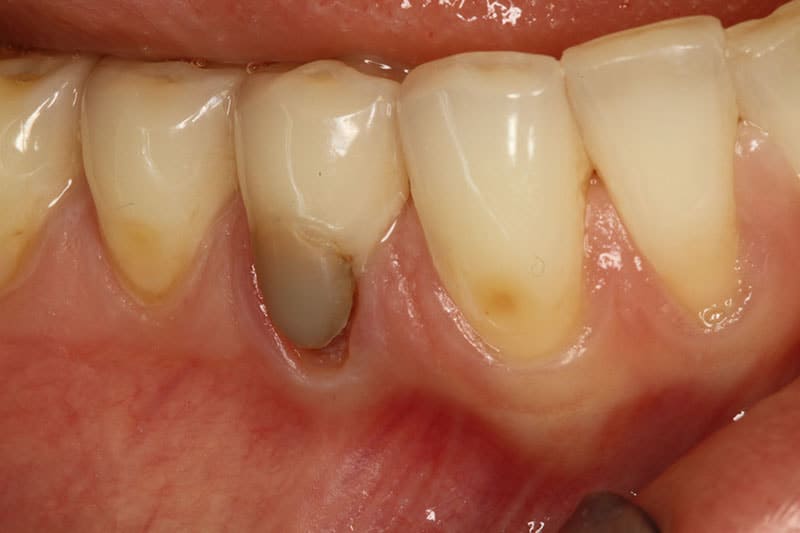

Before

After